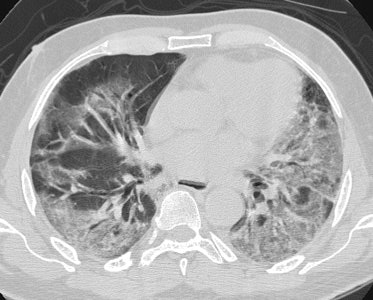

Acute interstitial pneumonia

The patient below presented with rapid onset respiratory failure. Chest CT revealed extensive areas of ground-glass attenuation/consolidation particularly in the dependent lung zones. A lung biopsy revealed acute interstitial penumonitis. |